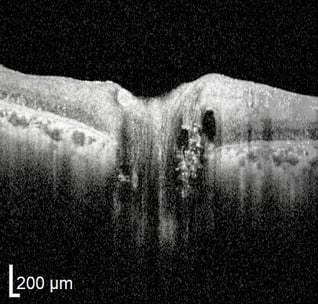

Makuladrusen sind das Kennzeichen der altersbedingten Makuladegeneration (AMD). Klinisch erscheinen Drusen als gelbe oder weiße Ablagerungen auf der Retina. Mit der OCT lassen Drusen sich als fokale Ablagerungen in der äußeren Netzhaut, zwischen der basalen Lamina des retinalen Pigmentepithels und der inneren kollagenen Schicht der Bruch‘schen Membran beobachten. Bei einer AMD im frühen oder mittleren Stadium ist normalerweise kein Schwund der Aderhaut zu beobachten. Bei fortgeschrittener AMD jedoch ist mitunter auch ein Schwund der Aderhaut festzustellen. Bei fortgeschrittener AMD werden auch andere retinale Anomalien durch das OCT sichtbar.

Atrophie des retinalen Pigmentepithels (RPE): Bei einer RPE-Atrophie kann man eine Pigmentmigration beobachten, bei der sich an einigen Stellen das RPE Material ansammelt, während es an anderen Stellen fehlt. Das RPE kann an Stellen mit Materialansammlung dicker werden und aufgrund einer Atrophie an andere Stelle dünner. Solche Veränderungen führen zu einer ungleichmäßigen Morphologie des RPE. Das RPE kann auch porös werden, was an Lücken oder Löchern in den Lagen selbst zu erkennen ist. Weniger oft kommt vor, dass eine neovaskuläre Membran der Aderhaut sich bildet und das RPE nach vorne schiebt.